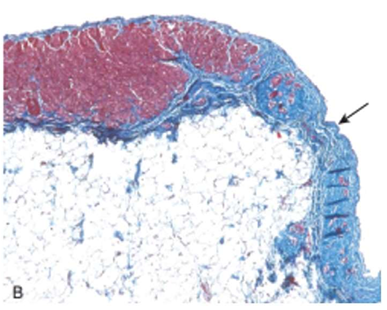

Dilated Cardiomyopathy

Myocyte hypertrophy and interstitial fibrosis (Blue with masson trichrome stain)